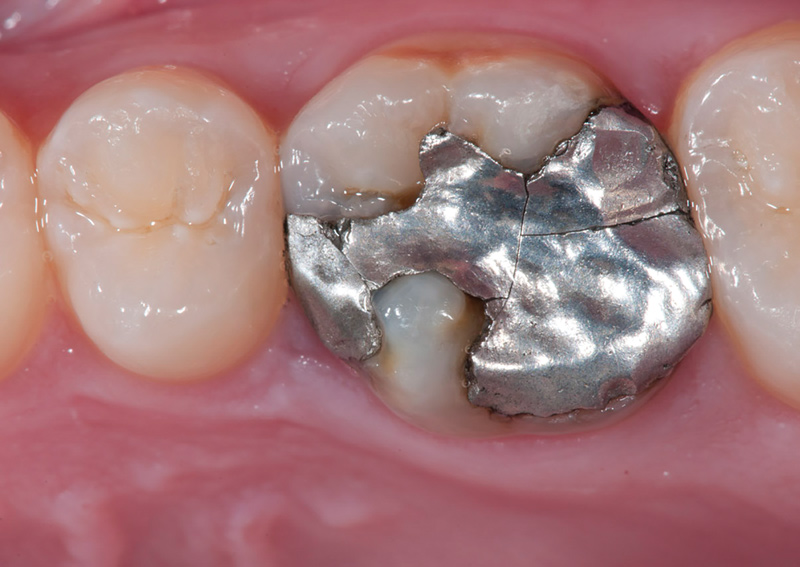

CL-IIIb high-strength 100% crystalline ceramics initially were alumina-based materials (Procera®, Nobel Biocare, nobelbiocare.com), and more recently zirconia-based materials (eg. LAVA™, 3M ESPE, 3mespe.com; Prettau®, Zirkonzahn, zirkonzahn.com). Alumina systems have proven successful for single units, but are being replaced by zirconia and lithium disilicate due to the increased risk of failure in the molar region.24,25 Zirconia can also be used when significant tooth structure is missing, when high risk for flexure and stress is present, for posterior full-crown and fixed partial denture situations (Figure 13 and Figure 14), and when adhesive bonding is problematic, such as with subgingival margins.

In cases where the bond and seal cannot be maintained (ie, high-risk bonding situations, including moisture control problems, high shear and tensile stresses on bonded interfaces, and variable bonding interfaces), high-strength CL-III ceramics or metal ceramics (CL-IV, see below) are appropriate, because they can be placed using conventional cementation techniques. A concern with full-contour zirconia, however, is wear on opposing dentition.26

Fig 15. Machined CL-IIIb zirconia framework prior to coloration and final sintering (Fig 15); colorized and final sintered monolithic CL-IIIb zirconia restoration (Fig 16) (images courtesy of Enrico Steger/Zirkonzahn).

Figure 15

Fig 16. Machined CL-IIIb zirconia framework prior to coloration and final sintering (Fig 15); colorized and final sintered monolithic CL-IIIb zirconia restoration (Fig 16) (images courtesy of Enrico Steger/Zirkonzahn).

Figure 16

Fig 17. Two-molar full-crown porcelain-fused-to-metal restoration made with a CL-IV substrate

Figure 17